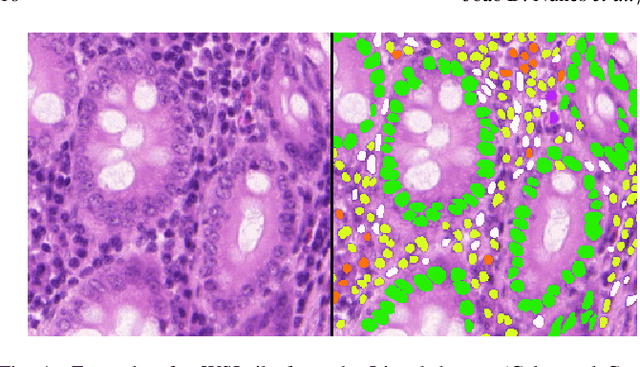

Abstract:Manually annotating nuclei from the gigapixel Hematoxylin and Eosin (H&E)-stained Whole Slide Images (WSIs) is a laborious and costly task, meaning automated algorithms for cell nuclei instance segmentation and classification could alleviate the workload of pathologists and clinical researchers and at the same time facilitate the automatic extraction of clinically interpretable features. But due to high intra- and inter-class variability of nuclei morphological and chromatic features, as well as H&E-stains susceptibility to artefacts, state-of-the-art algorithms cannot correctly detect and classify instances with the necessary performance. In this work, we hypothesise context and attention inductive biases in artificial neural networks (ANNs) could increase the generalization of algorithms for cell nuclei instance segmentation and classification. We conduct a thorough survey on context and attention methods for cell nuclei instance segmentation and classification from H&E-stained microscopy imaging, while providing a comprehensive discussion of the challenges being tackled with context and attention. Besides, we illustrate some limitations of current approaches and present ideas for future research. As a case study, we extend both a general instance segmentation and classification method (Mask-RCNN) and a tailored cell nuclei instance segmentation and classification model (HoVer-Net) with context- and attention-based mechanisms, and do a comparative analysis on a multi-centre colon nuclei identification and counting dataset. Although pathologists rely on context at multiple levels while paying attention to specific Regions of Interest (RoIs) when analysing and annotating WSIs, our findings suggest translating that domain knowledge into algorithm design is no trivial task, but to fully exploit these mechanisms, the scientific understanding of these methods should be addressed.

Abstract:Nuclear detection, segmentation and morphometric profiling are essential in helping us further understand the relationship between histology and patient outcome. To drive innovation in this area, we setup a community-wide challenge using the largest available dataset of its kind to assess nuclear segmentation and cellular composition. Our challenge, named CoNIC, stimulated the development of reproducible algorithms for cellular recognition with real-time result inspection on public leaderboards. We conducted an extensive post-challenge analysis based on the top-performing models using 1,658 whole-slide images of colon tissue. With around 700 million detected nuclei per model, associated features were used for dysplasia grading and survival analysis, where we demonstrated that the challenge's improvement over the previous state-of-the-art led to significant boosts in downstream performance. Our findings also suggest that eosinophils and neutrophils play an important role in the tumour microevironment. We release challenge models and WSI-level results to foster the development of further methods for biomarker discovery.